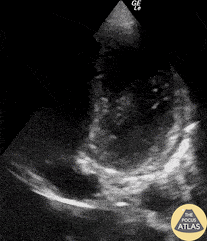

A young male presented with 2-day history of chest pain. His ECG revealed diffuse ST segment elevation. He had an elevated but serially stable troponin level. POCUS excluded focal wall motion abnormality though was notable for the presence of a small pericardial effusion and a thickened, hyperechoic pericardium; consistent with his diagnosis of acute pericarditis. Renato Melo, Emergency Physician @Renato_Melo_